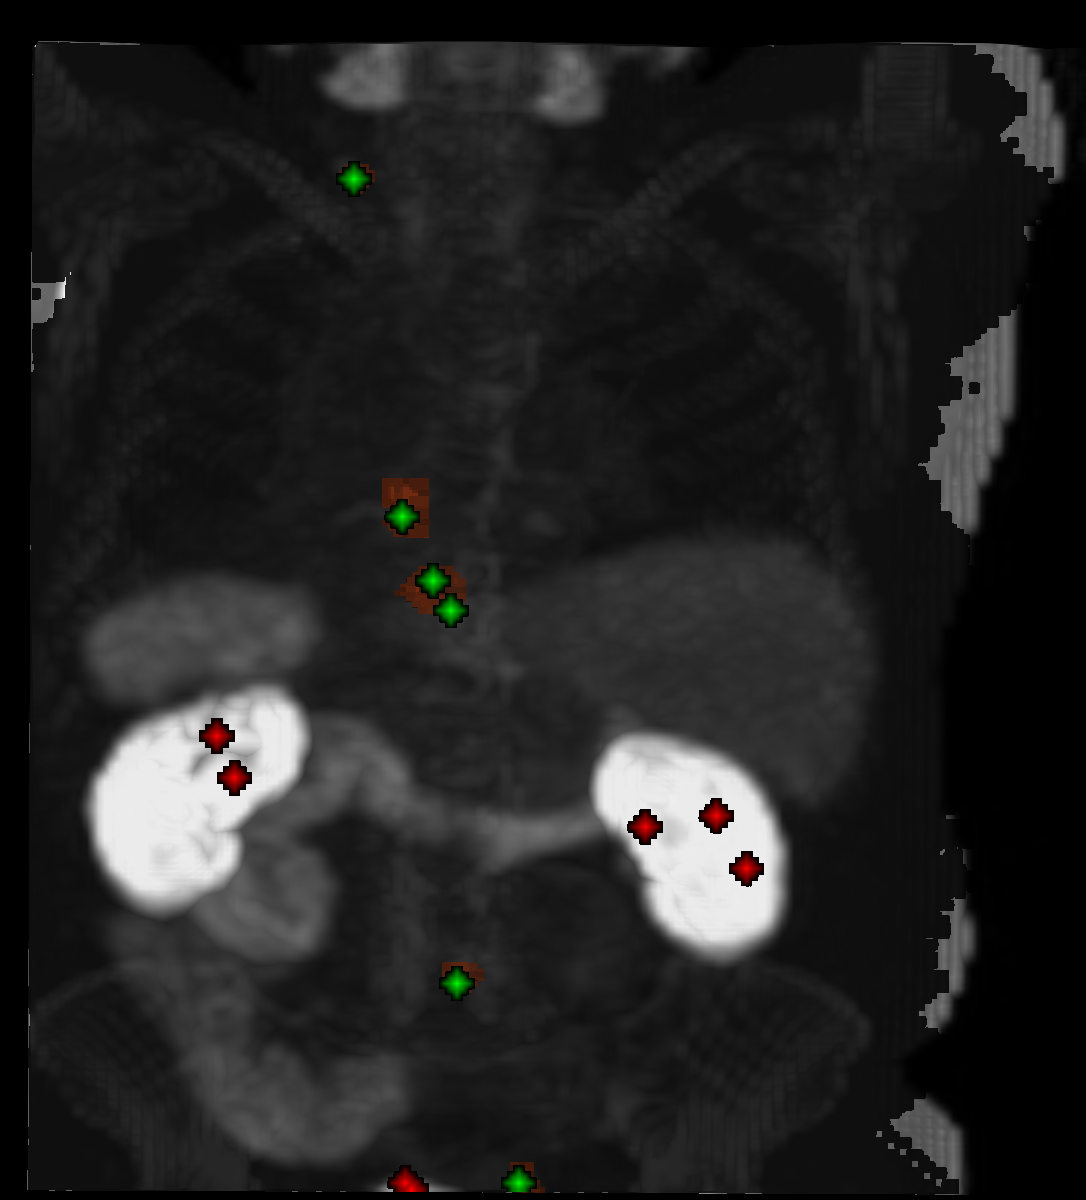

Figure 1: Examplary visualization of 3D image patches provided to the network during training with the respective positive (green) and negative (red) points as well as the ground truth segmentation mask shown.